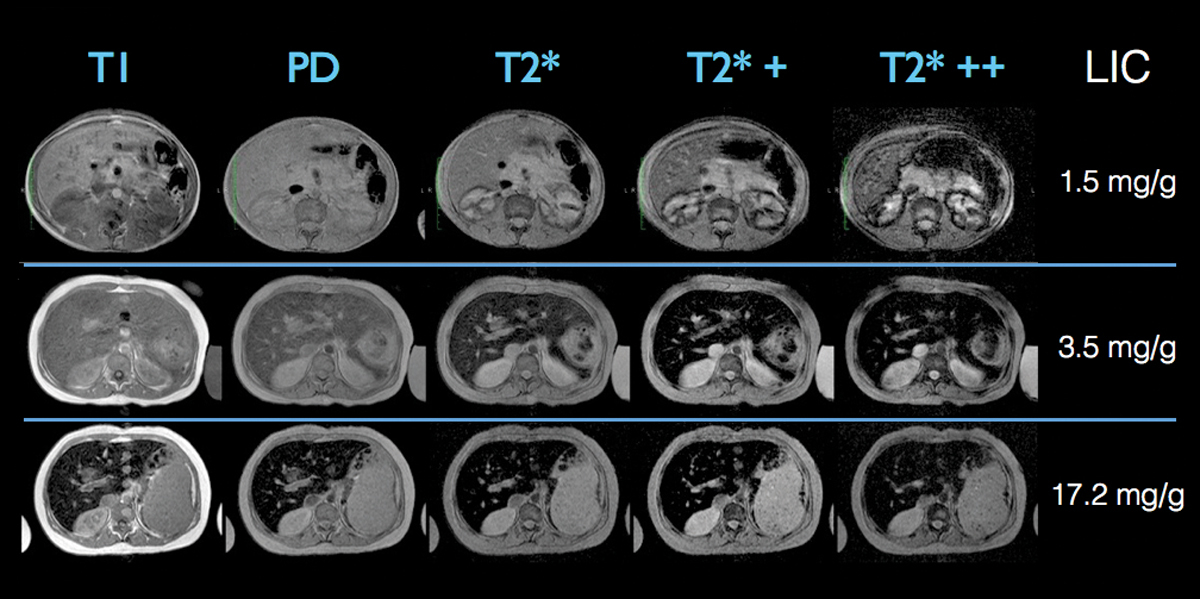

SIR, a third MRI imaging technique, may be performed to identify patients with milder iron overload. In SIR, gradient echo (GRE) image series of the abdomen are collected in five breath-holds. Regions of interest are drawn in the liver and paraspinous muscles. To generate LIC estimates, the values can be entered into a free web-based calculation tool from the University of Rennes, France [3, 59]. Calibration was derived from liver biopsies and shown in a highly T2-weighted GRE (GRE T2++) sequence, with the highest sensitivity (89%) and specificity (80%) and a good correlation (r = 0.87) between liver to muscle (L/M) SIR and LIC [51].

SIR is one of the earlier methods to assess LIC that is easy to perform, but has a severe limitation as it is only robust for low iron concentrations [59]. However, it is a good adjunct to R2 and R2* methods as it allows easy visual estimation of LIC, which is not possible with either R2 or R2* methods (fig. 2). In addition, SIR approaches are an option for screening purposes in primary haemochromatosis syndromes, particularly if relaxometry is not feasible [3]. Therefore SIR cannot replace R2 or R2* relaxometry, which is now the standard of care for tissue iron quantification. However, it can be useful especially when the quality of the relaxometry data is poor.

Figure 2 Example of three different patients examined with the SIR method composed of the acquisition of five gradients of echo images with a progressive sensitivity to iron content (T1 on the left is less sensitive to iron and is therefore affected only by high LIC. T2*++ on the right is sensitive to very small amounts of iron). LIC can be assessed quickly by sight, because the signal of the normal liver should be iso- or hyperintense to paravertebral muscle signal on all five MR sequences. In the case of iron overload, the signal of the liver is darker compared to paravertebral muscles. In the first patient (upper row) with no hepatic iron overload, the liver is hyperintense or isointense compared to the muscle on all the MR sequences reflecting a normal LIC. The second patient has a mild hepatic iron overload demonstrated by a liver signal lower than the muscle only in the T2* MR sequences. The third patient (lower row) has a significant iron overload that can be easily identified on the images since the liver is darker than the paravertebral muscles in all the MR sequences.